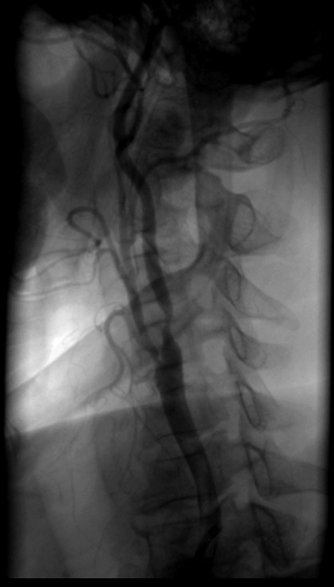

5.2 Chụp và can thiệp mạch máu ngoại biên:

Nong bóng, đặt stent giúp giải quyết các tổn thương hẹp, tắc ĐM cảnh gây thiếu máu não, ĐM thận gây suy thận, ĐM chi gây thiếu máu nuôi chi… Đặt stent graft động mạch chủ ngăn ngừa vỡ phình động mạch chủ lớn…

Trước can thiệp Sau can thiệp

Một trường hợp hẹp nặng ĐM cảnh trong giải quyết tốt bằng Wallstent